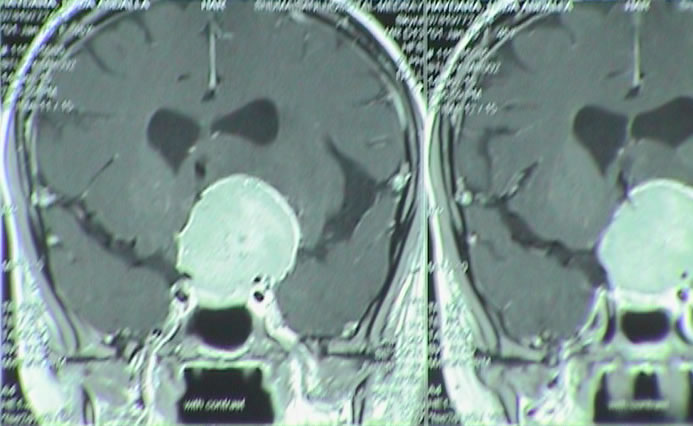

Another case with massive suprasellar extension: The patient came 36 years old to the clinic 14-December-2017 complaining of blurred vision left eye for three years. The last week go almost blind left eye with decreased vision right eye. MRI done in Turkey 11-December-2017 showing huge pituitary adenoma with massive infrasellar and moderate suprasellar extension with signs of apoplexy of the tumor bed with fluid level inside the tumor. The patient is convulsion free.

The patient was sent for thorough radio-ophthalmo-endocrine investigations. MRI of the sella with MRA done 16-December-2017 showed the tumor pushing the chiasm and optic nerves with suprasellar extension around 16.2 mm. The tumor has massive infrasellar extension reaching the naso-pharyngeal space abutting it. The tumor dimensions are 37.3x28.6 mm. There is no invasion of the cavernous sinuses. There is fluid level inside the tumor confirming the presence of apoplexy. Visual acuity of the right eye after correction 6/6. The left eye 6/0.05. There is massive scatoma left eye with less in the right eye. Prolactine 470 ng/ml, LH 1.19, testosterone 0.3. Considering the above data trans-sphenoidal approach with MRI control was advised. Mathematically speaking the volume of the tumor with the hypophysis is around 8.8 ml.

Fig-26:- Preoperative MRI Showing the huge suprasellar extension.

Fig-27:  Preoperative MRI Saggital view.

Fig-29: The tumor resected. Notice the swollen pituitary stalk .